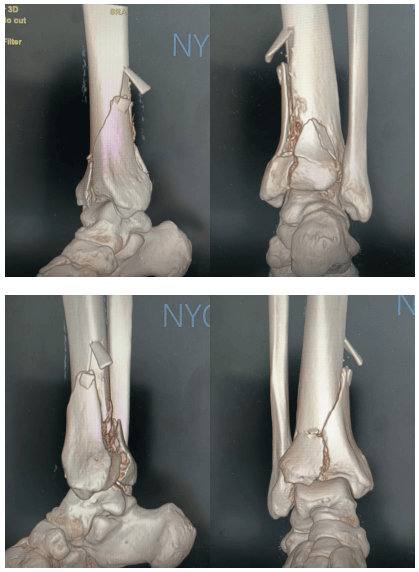

影像结果显示,韩师傅的右胫骨远端关节面发生了粉碎性骨折,同时合并腓骨骨折。

这种骨折在医学上称为“皮隆(Pilon)骨折”,简单来说,就是小腿骨靠近脚踝的那一端被“压碎”了。它通常由高处坠落、车祸等高能量损伤引起,是脚踝骨折中比较严重的一种类型。如果处理不当,容易出现关节面不平整、创伤性关节炎、脚踝僵硬等后遗症。

经过一段时间的消肿治疗,待局部软组织条件改善后,医生才着手制定手术方案。术前,团队借助CT三维重建技术,清晰还原了骨折块的位置、大小和关节面塌陷的程度,并通过术前规划模拟,精准设计了手术入路和内固定方案。